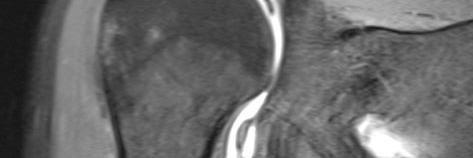

Direkte kontrastverstärkte MRT-Arthrografie Schulter

Kontrastmittel wird direkt ins Gelenk injiziert, um Knorpeloberflächen, Kapsel- und Meniskusrisse besser darzustellen. Die Injektion erfolgt meist unter Röntgen-Durchleuchtung mit örtlicher Betäubung.

Häufigste Anwendungen: Darstellung von Kapsel-Bandrissen im Schultergelenk oder Ellebogengelenk, Pfannenrandrisse und andere Gelenkbinnenschäden am Hüftgelenk, Diskus- und Bandläsionen am Hangelenk.